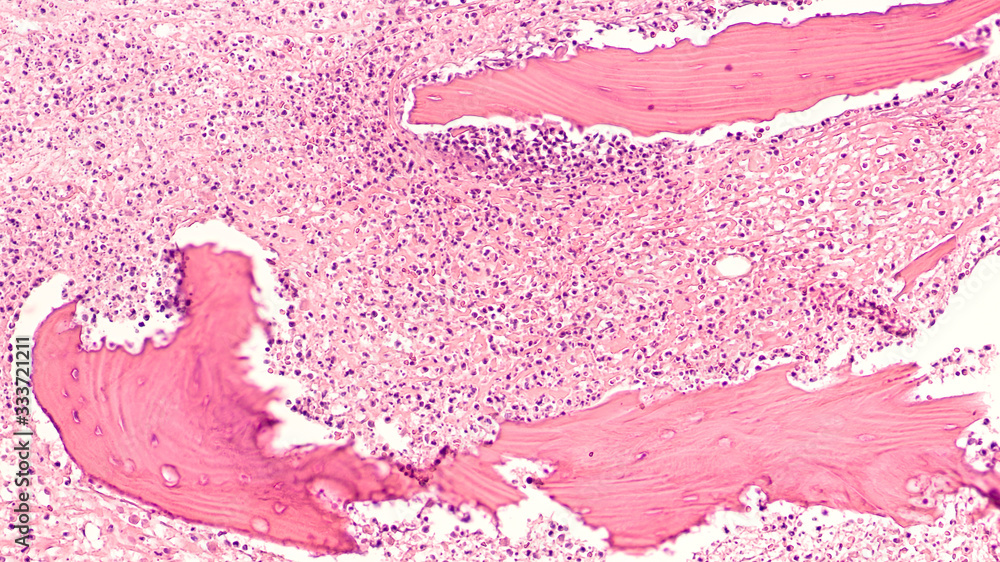

Diabetes Awareness Photomicrograph showing osteomyelitis, with Osteomyelitis Of The Jaw Histology Histopathologic examination of bone specimens coupled with bone culture is considered the gold standard for the diagnosis of osteomyelitis. Osteomyelitis is an infectious disease affecting bone and bone marrow, 1 with staphylococcus aureus being the causative. Primary chronic osteomyelitis of the jaw is a rare, nonsuppurative, chronic inflammation of an unknown cause. The classic clinical presentation consists of pain, swelling,.. Osteomyelitis Of The Jaw Histology.